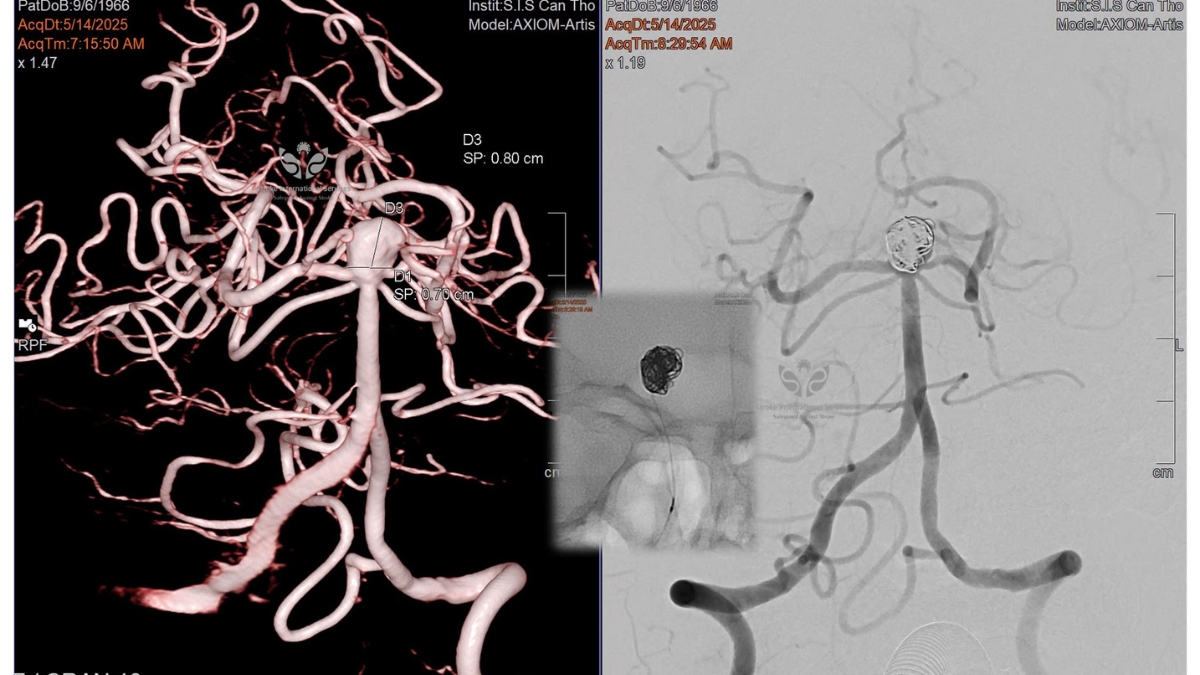

Bệnh nhân tiếp tục được chỉ định chụp cộng hưởng từ (MRI) để đánh giá nhu mô não và khảo sát chi tiết túi phình. Kết quả ghi nhận túi phình khá lớn, kích thước khoảng 7x8mm và có biểu hiện lâm sàng – điều này cho thấy cần can thiệp sớm để phòng ngừa nguy cơ vỡ phình, gây xuất huyết dưới nhện hoặc đột quỵ đe dọa tính mạng.

Hướng điều trị được đặt ra ban đầu bao gồm các lựa chọn như đặt stent kết hợp coils, sử dụng hệ thống WEB (thiết bị đóng túi phình thế hệ mới), hoặc phối hợp nhiều kỹ thuật khác. Tuy nhiên, bất ngờ lớn xảy ra khi kíp can thiệp xác định có thể xử lý chỉ bằng 5 coils đơn thuần, không cần đến stent hay thiết bị hỗ trợ đặc biệt nào khác. Toàn bộ ca can thiệp diễn ra thuận lợi, an toàn, và túi phình được loại bỏ hiệu quả.

Hình ảnh túi phình đỉnh động mạch thân nền can thiệp thành công bằng kỹ thuật đặt coils tại Bệnh viện Đa khoa Quốc tế S.I.S Cần Thơ